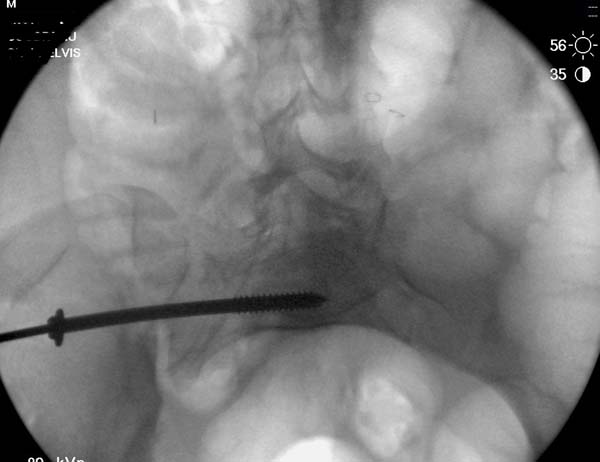

Но вам повезло, двумя винтами смогли зацепить и репонировать

переломо-вывих. Обычно такие переломы надо фиксировать спереди или сзади

пластиной или шурупом, т.е. создать дополнительную стабильность крыла,

кроме  перкутанной фиксации.

Здесь примеры фиксации с различными вариантами.... .